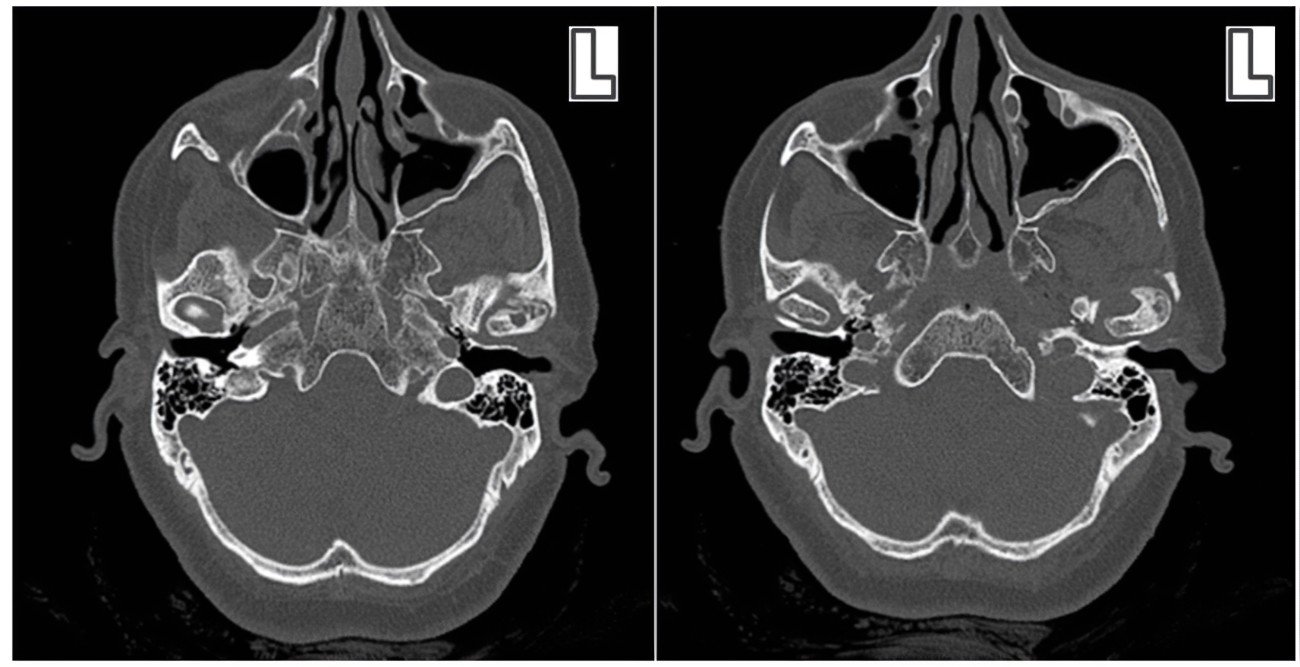

- Arthritis

Clinical Presentation: Pain and stiffness in the TMJ, swelling, and reduced range of motion.

Zebris Findings: Degenerative changes in the condyles, irregularities in joint movement, and decreased joint space.

Zebris vs. Static Imaging (X-rays, CBCT):

- Static imaging shows anatomical structures but not functional movement

- Zebris captures dynamic function but not detailed anatomy

- Combined approach often provides the most comprehensive diagnosis